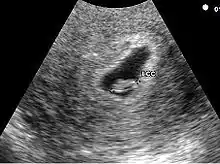

Embryon à 5 semaines

L'embryon est visible dès 5 semaines en cas d'utilisation de sonde endovaginale de haute fréquence. Il se présente comme une zone hyperéchogène coincée entre la vésicule vitelline et la paroi du sac ovulaire. Une activité cardiaque peut être visualisée. Il est déconseillé, à ce stade, d'utiliser le doppler pour entendre l'activité cardiaque embryonnaire en raison d'effet délétère possible sur la formation du cœur. En raison de la sensibilité humaine au mouvement, il est parfois possible de visualiser une activité cardiaque avant la visualisation de l'embryon. En pratique, l'activité cardiaque doit être systématiquement vue dès que l'embryon mesure 5 mm.